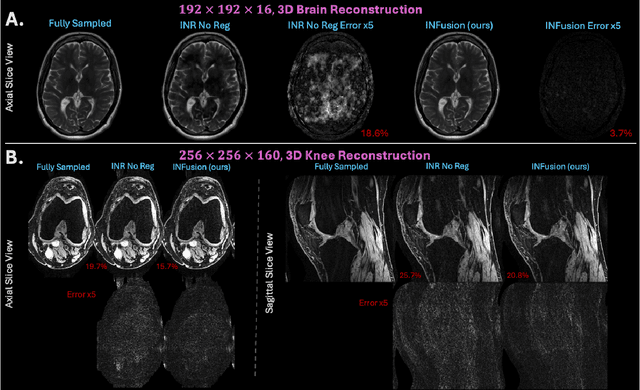

Abstract:Implicit Neural Representations (INRs) are a learning-based approach to accelerate Magnetic Resonance Imaging (MRI) acquisitions, particularly in scan-specific settings when only data from the under-sampled scan itself are available. Previous work demonstrates that INRs improve rapid MRI through inherent regularization imposed by neural network architectures. Typically parameterized by fully-connected neural networks, INRs support continuous image representations by taking a physical coordinate location as input and outputting the intensity at that coordinate. Previous work has applied unlearned regularization priors during INR training and have been limited to 2D or low-resolution 3D acquisitions. Meanwhile, diffusion based generative models have received recent attention as they learn powerful image priors decoupled from the measurement model. This work proposes INFusion, a technique that regularizes the optimization of INRs from under-sampled MR measurements with pre-trained diffusion models for improved image reconstruction. In addition, we propose a hybrid 3D approach with our diffusion regularization that enables INR application on large-scale 3D MR datasets. 2D experiments demonstrate improved INR training with our proposed diffusion regularization, and 3D experiments demonstrate feasibility of INR training with diffusion regularization on 3D matrix sizes of 256 by 256 by 80.